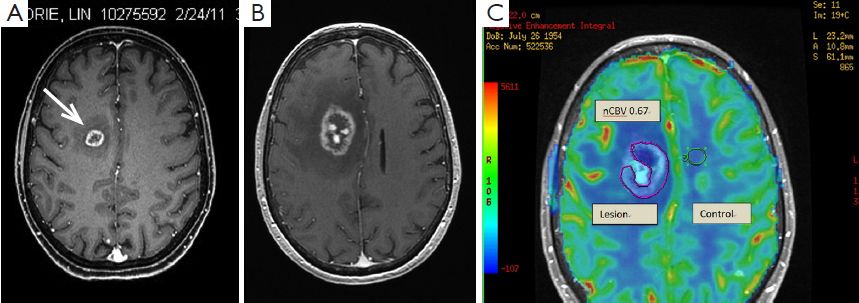

脑放射性坏死的另一个麻烦是,与脑转移瘤复发难以区分。脑肿瘤由于缺乏血管,中心往往也有明显的坏死区,这就让影像科医生犯了难——究竟是放射导致的坏死,还是转移癌复发了?

对医生来说,这两种情况表现出的症状差不多,临床上也难以鉴别。对患者来说,无论是放射性坏死误诊为脑肿瘤,还是肿瘤误诊为坏死,都是不可接受的,前者引起过度治疗,后者则会贻误病情。

怎么办呢?我们需要有经验的影像科医生帮忙,有时还需要使用PET扫描来鉴别。